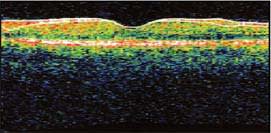

A 74 year-old male with a 15 year history of non-insulin-dependent diabetes presented for a routine cataract procedure. There were no intraoperative complications and he did very well post-procedure. At the time of his 1-month postoperative exam, his vision had declined to 20/70. Optical coherence tomography (OCT) revealed classic cystoid macular edema (CME).

Figure 1. Typical cystic spaces confirming the diagnosis of CME (abnormal).